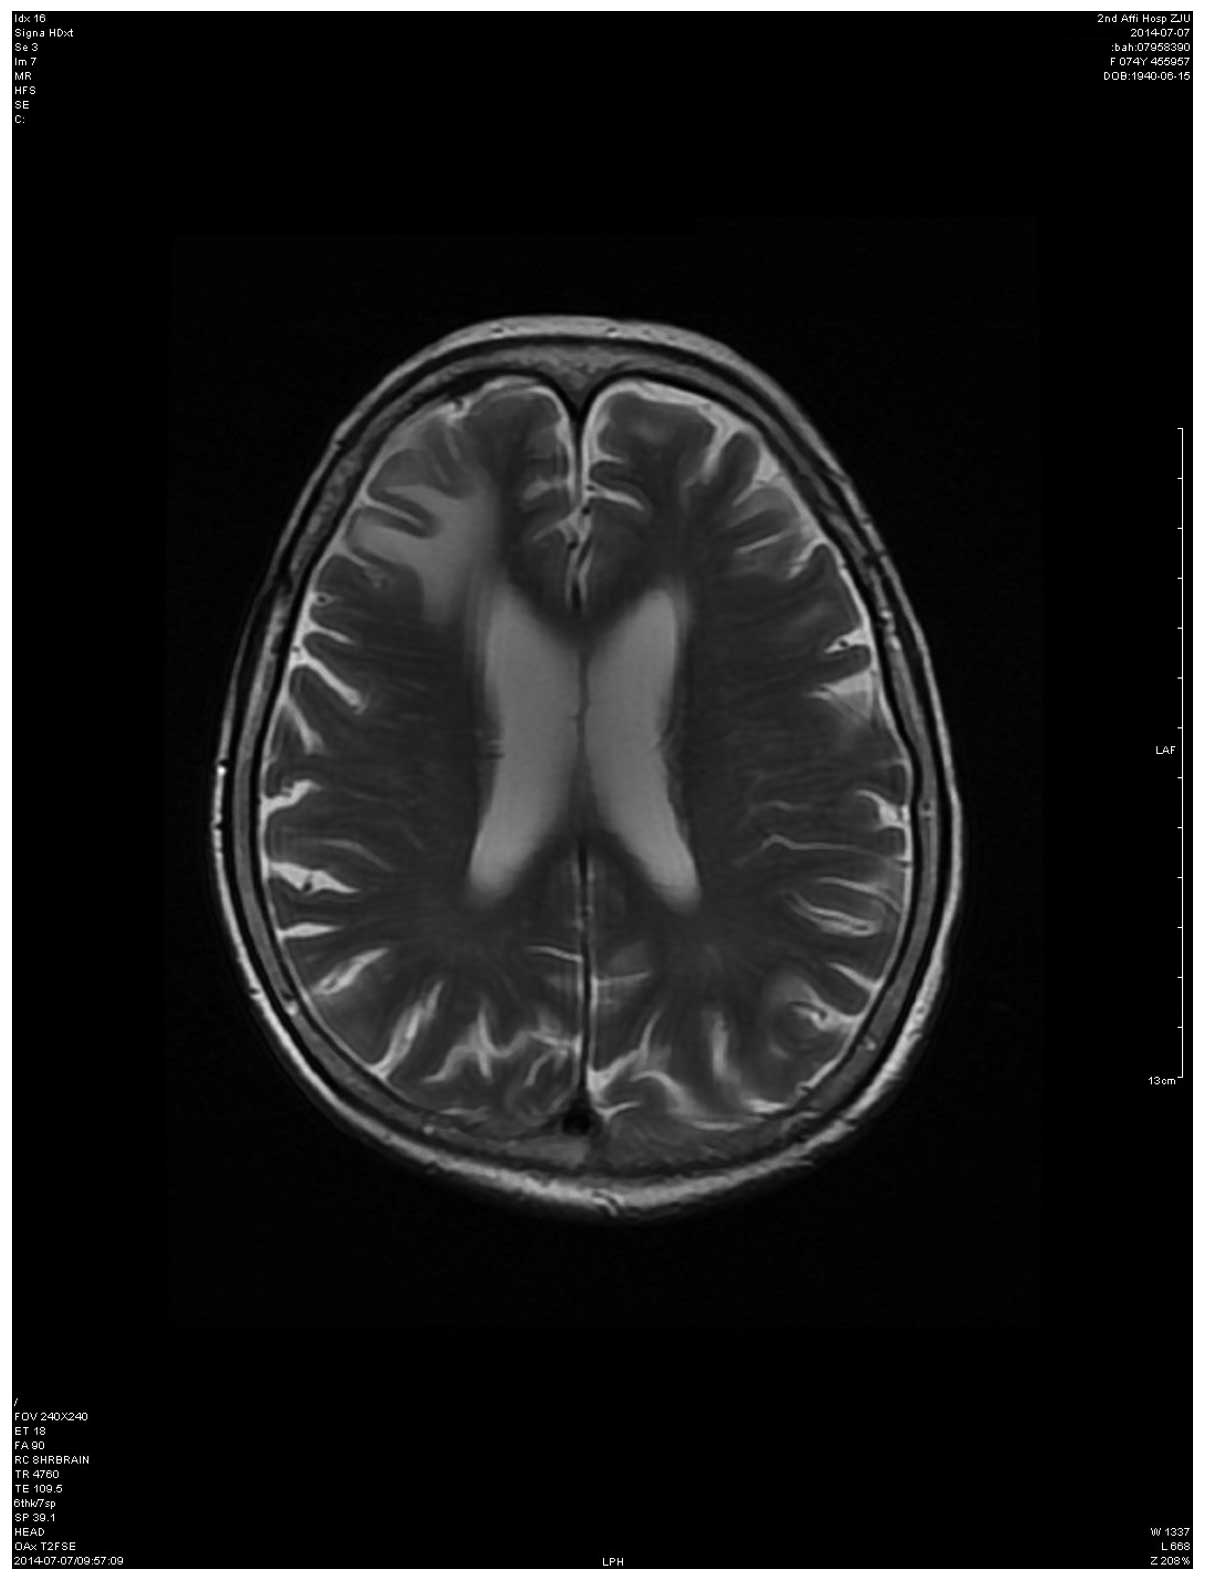

Over 4 months later, the patient underwent a follow-up brain MRI scan, which revealed that the metastatic lesion was significantly smaller compared with prior to treatment (Fig. 2). In October, 2014, the patient remained alive and was continuing icotinib therapy, without other chemotherapies.

Figure 2.

Contrast-enhanced magnetic resonance imaging after 4 months of epidermal growth factor receptor-tyrosine kinase inhibitor treatment, showing substantial regression of the metastatic lesion.